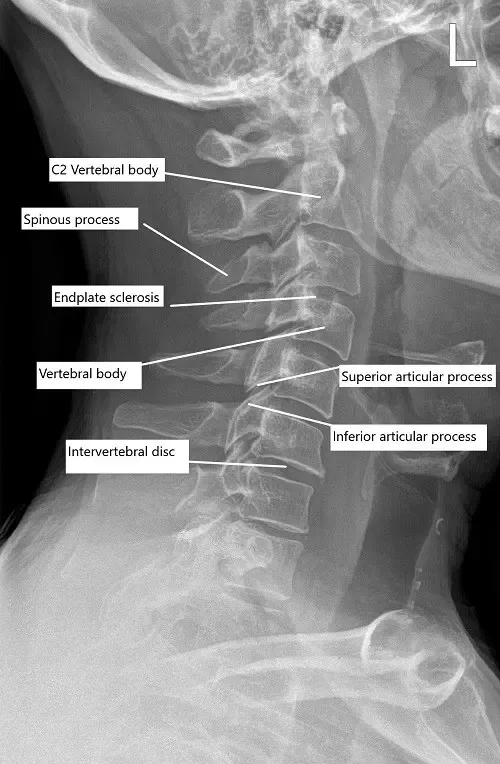

Radiografía preoperatoria de la columna cervical en vista lateral